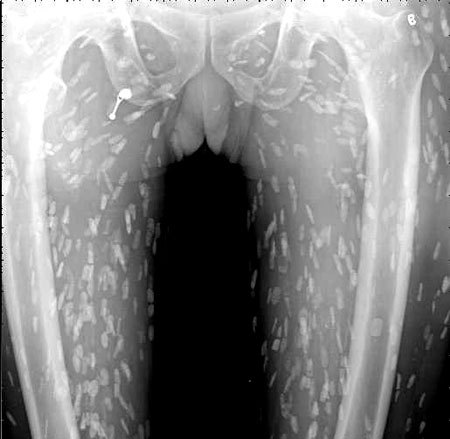

브라질의 한 의료진이 소셜네트워크서비스(SNS)에 기생충에 감염된 엑스레이 사진을 공개했습니다. 사진에는 몸속에 있는 기생충이 죽어 석회화된 수백 개의 점 형상이 보였습니다.

특히 유충이 근육이나 뇌 조직에 침투한 모습은 매우 충격적이었습니다. 이러한 증상은 유구조충의 유충에 의한 인체감염증으로, 유구 낭미충증이라고도 불립니다.

유구낭미충증은 주로 인간의 장에 사는 촌충의 유충이 근육이나 뇌로 침투할 때 발생합니다. 이 유충은 근육과 뇌에서 낭종과 같은 결절을 형성하기도 합니다.

의료진은 해당 환자가 특별한 치료를 받지 않았다고 밝혔습니다. 그는 "머리, 척수, 눈에 이상이 없는 한 치료가 필요하지 않습니다"라며 "해당 물체들은 석회화되어 있어 생존 가능한 유충이 아닙니다. 불편함을 느끼지 않는다면 특별한 조치가 필요하지 않습니다"라고 말했습니다. 그러나 해당 환자의 뇌에 낭종이 있는지 확인하기 위해 MRI 검사를 기다리고 있다고 전했습니다.